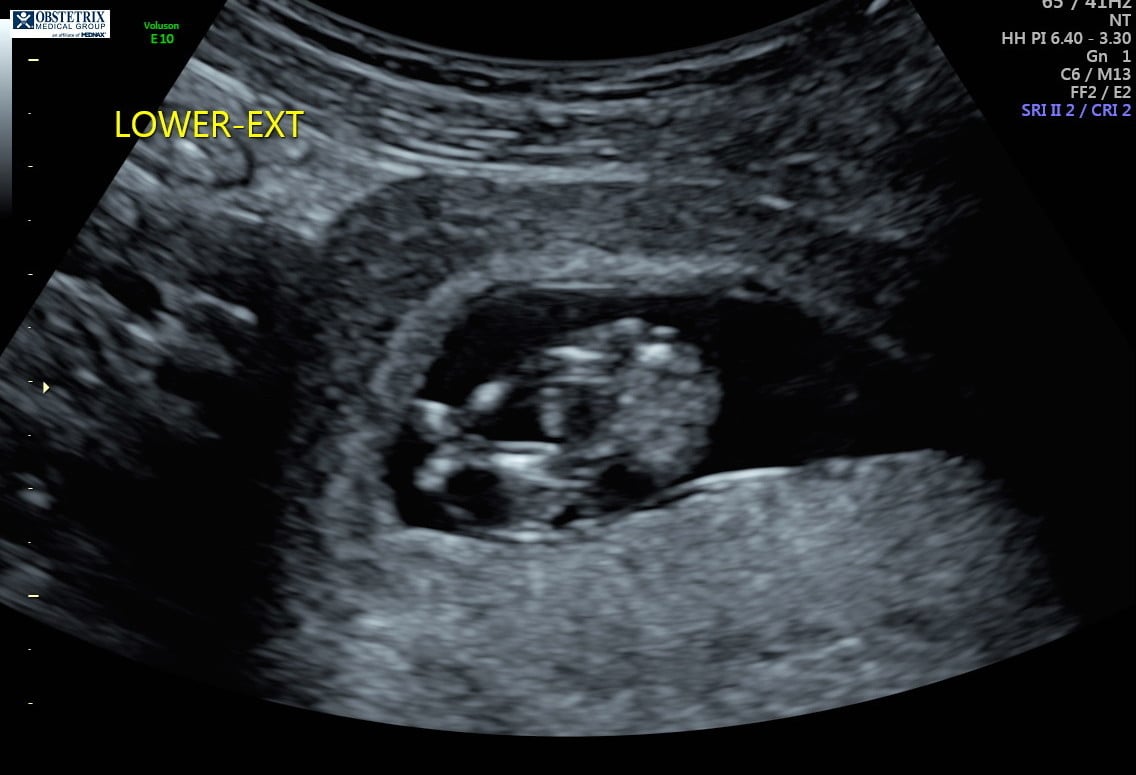

Hello! The photo is from my 12 week ultrasound. I’ve been reading up on the nub theory because I’m dying to know the sex, but I can’t decide if it looks more girly or boyish. Any thoughts are appreciated!!!!

“Experts” on the nub theory my friend. Yes, I have talk to doctors about it. Yes, some do believe in the nub theory while others are afraid to guess because they are afraid to guess wrong and upset anyone which makes sense. No, it is not always accurate and if you try the nub theory generally you know not to take to it too seriously until the anatomy scan. Also this theory will not hurt the baby so no harm done. But if you can’t handle the possibilty of a wrong guess then don’t even try asking for a guess. It’s for fun. Have you read up on it even? The nub sits flat with the back if it’s a girl and it’s angled up from the back if it’s a boy. I have 2 girls and 1 boy so I am pretty sure it’s not “luck” just really good scans! The “experts” on the nub theory have guessed correctly with my ultrasound pictures. I have also done the NT scans which is around the right time to make a guess with the nub about 11-13 weeks I believe. The doctor agreed that it can be accurate if done properly. You must have a perfect nub picture ( a full body side view of fetus without their back curled during 11-13 weeks) to get a pretty accurate guess. Notice my use of guess? Yes, still 50/50 and yes, doctors still get the anatomy scan wrong too so you can’t be 100% sure until birth if you are want total accUracy. Do some reading up. I found it very interesting when I had my first child. But it is called a theory for reason.

Thanks so much for the input habrsk87! I completely agree with all you have said. As I mentioned previously, I totally was just posting this for fun. I was not going to hold anyone accountable if they guessed wrong... lol. The nub theory just seemed to be a bit more “scientific” than the other gender guessing myths (please note hat scientific is in quotes as I couldn’t find any legit studies proving the accuracy rate the theory boasts). I didn’t ask my doctor when she was doing the US if she could tell the gender as I didn’t read up on the nub theory until after the scan. Again, everyone this was just for fun and nothing more! Please don’t take the question too seriously. Thank you everyone for your thoughts and input!!